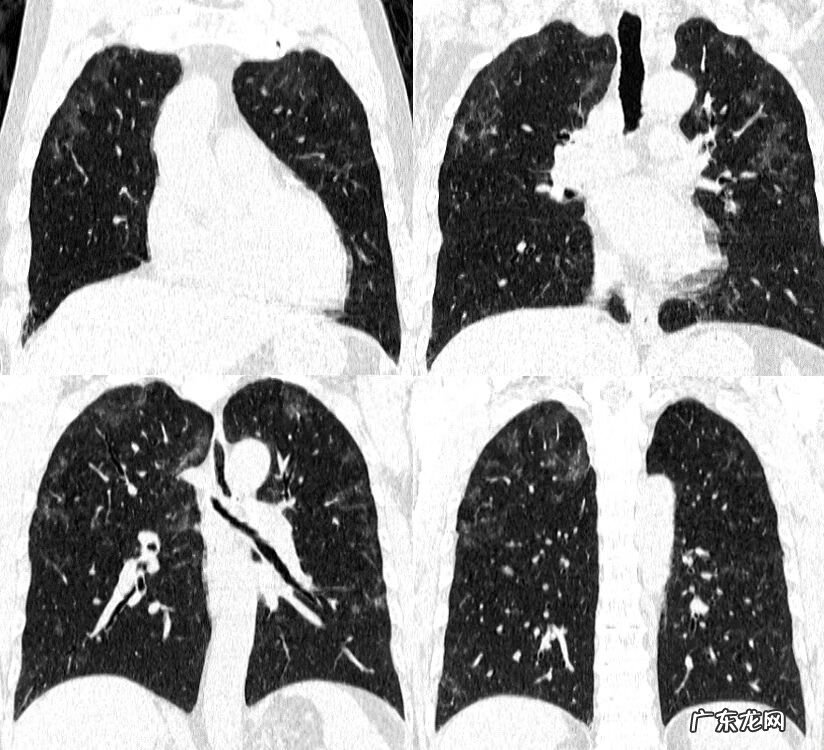

来看一下,治疗20天复查

肺内病变部分吸收,部分残留,磨玻璃影仍然是主要征象,分布仍然是以胸膜下为主,沿支气管血管束 。